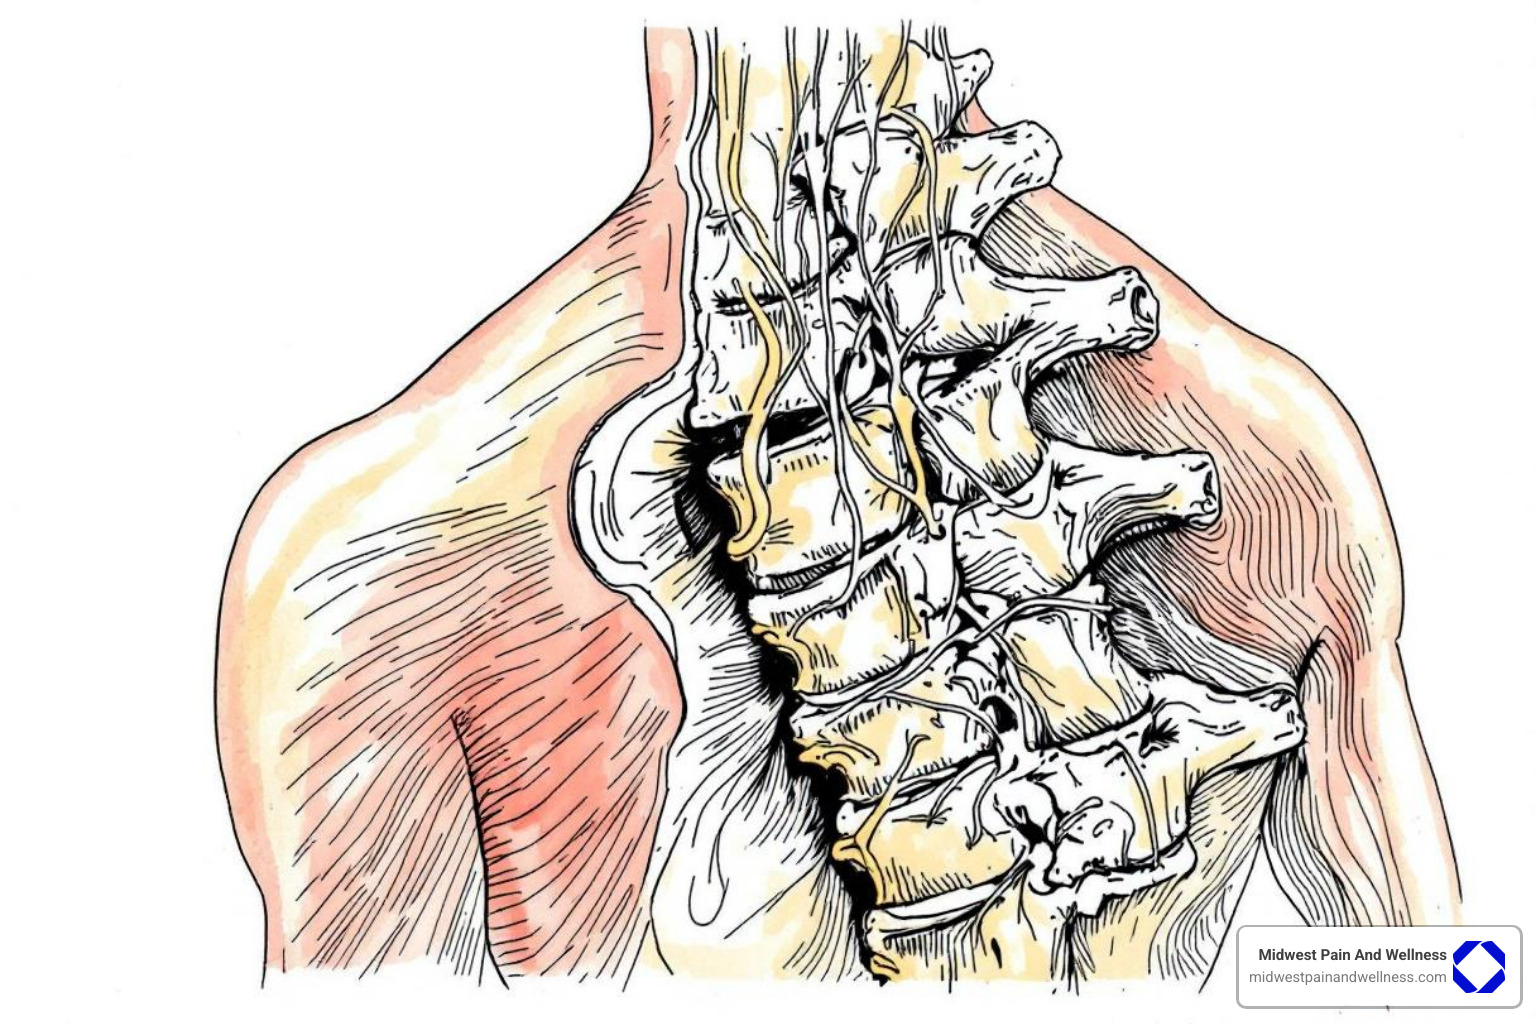

To better visualize this condition, here’s an image illustrating the narrowing that occurs:

Spinal stenosis is a structural condition involving the narrowing of the spinal canal. This canal protects your spinal cord and nerve roots. When it narrows, it puts pressure on these delicate structures, unlike sciatica, which is a symptom of nerve compression.

This narrowing is most common in the lower back (Lumbar Stenosis) and neck (Cervical Stenosis). We will focus on lumbar stenosis due to its symptom overlap with sciatica.

This happens when the narrowing in the lumbar spinal canal irritates or compresses the specific nerve roots that form the sciatic nerve. Therefore, sciatica can be a symptom of underlying spinal stenosis, not just a result of a herniated disc.

- Nerve root irritation: Constant pressure or inflammation around the nerve roots can cause them to send pain signals down the leg.

- Nerve compression: In severe stenosis, the restricted space directly compresses the nerve, leading to pain, numbness, and weakness.